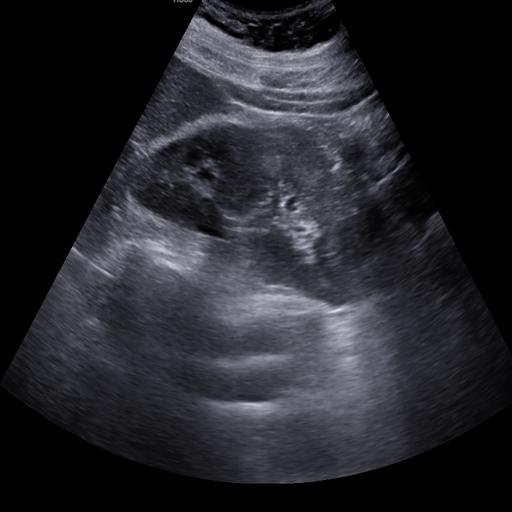

数据样例

结石肾脏样例